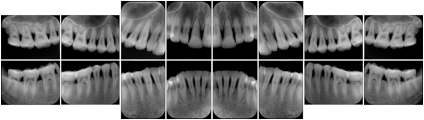

OO.1.4 Radiology

• A radiologist on his PACS assembles a screen layout of a stack of CT images of a current lung study, a secondary capture of a 3-D rendering of the CT, and a prior chest radiograph for the patient. He adjusts the window width / window level for the CT images, and zooms and annotates the radiograph to clearly indicate the tumor. He saves a Structured Display object representing that screen layout, including Grayscale Softcopy Presentation State objects for the CT WW/WL and the radiograph zoom and annotation. During the weekly radiology department conference, on an independent (non-PACS) workstation, he accesses the Structured Display object, and the display workstation automatically loads and places the images on the display, and presents them with the recorded WW/WL, zoom settings, and annotations.

• A mammographer reviews a screening exam on a mammo workstation. She wishes to discuss the exam with the patient's general practitioner, who does not have a mammo-specific workstation. She saves a structured display, with presentation states for each image that replicate the display rendered by the mammo workstation (scaling, horizontal and vertical alignment, view and laterality annotation, etc.).

Mammography Structured Display

Figure OO-7. Mammography Structured Display